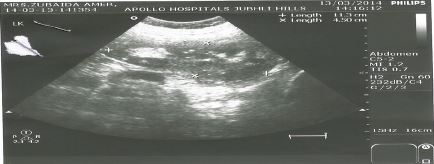

Investigation also showed serum calcium range from 2.85-3.0 mmol/L (2.13-2.63), phosphorus 0.7 mmol/L (0.8, 1.4) and magnesium 0.6 mmol/L (0.74, 1). The mean parathyroid hormone level (PTH) was above 30.4 pmol/L (1.69-6.9) or 198.5 pg/ml (15-65), which confirmed our suspicion of hyperparathyroidism. In addition the calcium to creatinine ratio was increased to 0.11 (normal limit < 0.06). Abdominal ultrasound showed multiple right renal calculi and mild hydronephrosis (see Figure 2); and neck ultrasound showed a low echogenic mass (1.3x1.5x3.3 cm) that intensified suspicion of a right inferior parathyroid adenoma (see Figure 3).

Figure 2: Abdominal ultrasound showing right renal stone

Figure 2: Abdominal ultrasound showing right renal stone